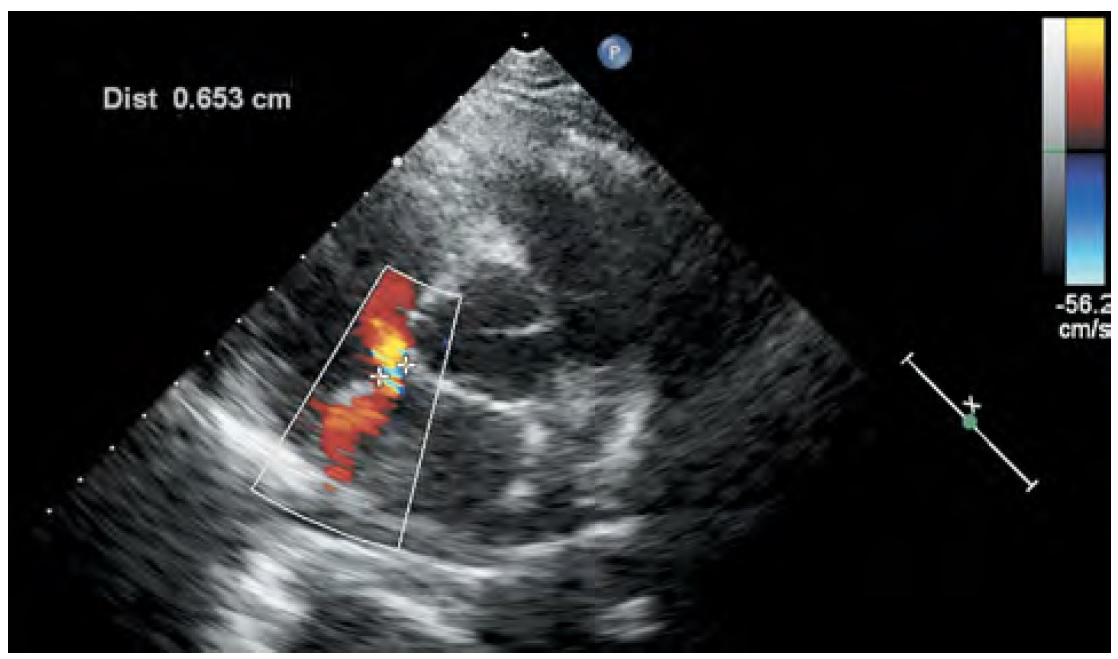

Трансторакальная эхокардиография (ТТЭхоКГ) — это основной метод визуализации ДМПП и оценки его размера, расположения, направления шунтирования крови и гемодинамической значимости (рис. 1) [4]. Определение вида ДМПП (первичный, вторичный или дефект венозного синуса) также проводится с помощью ТТЭхоКГ. Чреспищеводная эхокардиография (ЧПЭхоКГ) может быть использована для исключения других причин кардиоэмболического инсульта (таких как внутрисердечные тромбы или опухоли, инфекционный эндокардит, атерома дуги аорты), которые могут быть не диагностированы при ТТЭхоКГ, а также для определения более точной локализации ДМПП и дальнейшей тактики хирургического лечения.

Рис. 1. Трансторакальная эхокардиография. Парастернальная позиция по короткой оси аорты. При цветовой допплерографии в межпредсердной перегородке визуализируется вторичный ДМПП со сбросом крови слева- направо максимальным размером до 6,5 мм. / Fig. 1. Transthoracic echocardiography. Parasternal short-axis view. Colour Doppler ultrasound of the atrial septum reveals a secondary ASD with a right-to-left blood shunt and a maximum size of 6.5 mm.